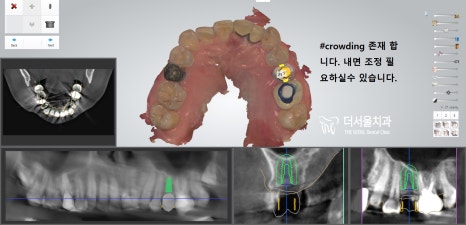

본격적인 수술을 진행하기 전,

환자께 왜 해당 술식을 선택하셨는지 여쭤보았습니다.

이분께서는 상악 소구치 부위에

식립을 필요로 하는 상황이었는데요.

상악동이 아래로 내려와 있어서

거상술을 동반하기로 했습니다.

컴퓨터 분석을 진행하고 난 뒤,

계산된 위치에 픽스처를 심어드렸습니다.

다행히 올곧게 잘 심어져 있는 모습이네요ㅎㅎ